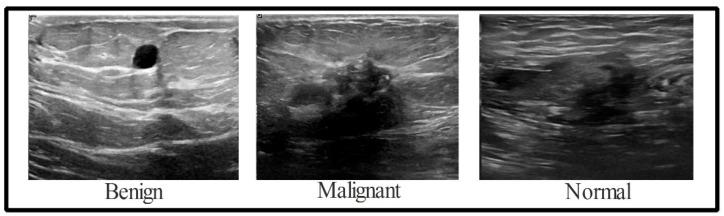

According to the American Cancer Society, breast cancer is the second largest cause of mortality among women after lung cancer. Women's death rates can be decreased if breast cancer is diagnosed and treated early. Due to the lengthy duration of manual breast cancer diagnosis, an automated approach is necessary for early cancer identification. This research proposes a novel framework integrating metaheuristic optimization with deep learning and feature selection for robustly classifying breast cancer from ultrasound images. The structure of the proposed methodology consists of five stages, namely, data augmentation to improve the learning of convolutional neural network (CNN) models, transfer learning using GoogleNet deep network for feature extraction, selection of the best set of features using a novel optimization algorithm based on a hybrid of dipper throated and particle swarm optimization algorithms, and classification of the selected features using CNN optimized using the proposed optimization algorithm. To prove the effectiveness of the proposed approach, a set of experiments were conducted on a breast cancer dataset, freely available on Kaggle, to evaluate the performance of the proposed feature selection method and the performance of the optimized CNN. In addition, statistical tests were established to study the stability and difference of the proposed approach compared to state-of-the-art approaches. The achieved results confirmed the superiority of the proposed approach with a classification accuracy of 98.1%, which is better than the other approaches considered in the conducted experiments.

根据美国癌症协会的数据,乳腺癌是女性中仅次于肺癌的第二大死因。如果乳腺癌能够早期诊断和治疗,女性的死亡率可以降低。由于人工诊断乳腺癌的时间较长,因此需要一种自动化方法来早期识别癌症。本研究提出了一种新颖的框架,将元启发式优化与深度学习和特征选择相结合,以从超声图像中稳健地分类乳腺癌。所提出方法的结构包括五个阶段,即数据增强以改进卷积神经网络(CNN)模型的学习、使用谷歌网络深度网络进行迁移学习以进行特征提取、使用基于双喉和粒子群优化算法混合的新颖优化算法选择最佳特征集,以及使用所提出的优化算法优化的CNN对所选特征进行分类。为了证明所提出方法的有效性,在Kaggle上免费提供的乳腺癌数据集上进行了一组实验,以评估所提出的特征选择方法的性能和优化后的CNN的性能。此外,还建立了统计测试来研究所提出方法与现有方法相比的稳定性和差异。所取得的结果证实了所提出方法的优越性,分类准确率达到98.1%,优于所进行实验中考虑的其他方法。